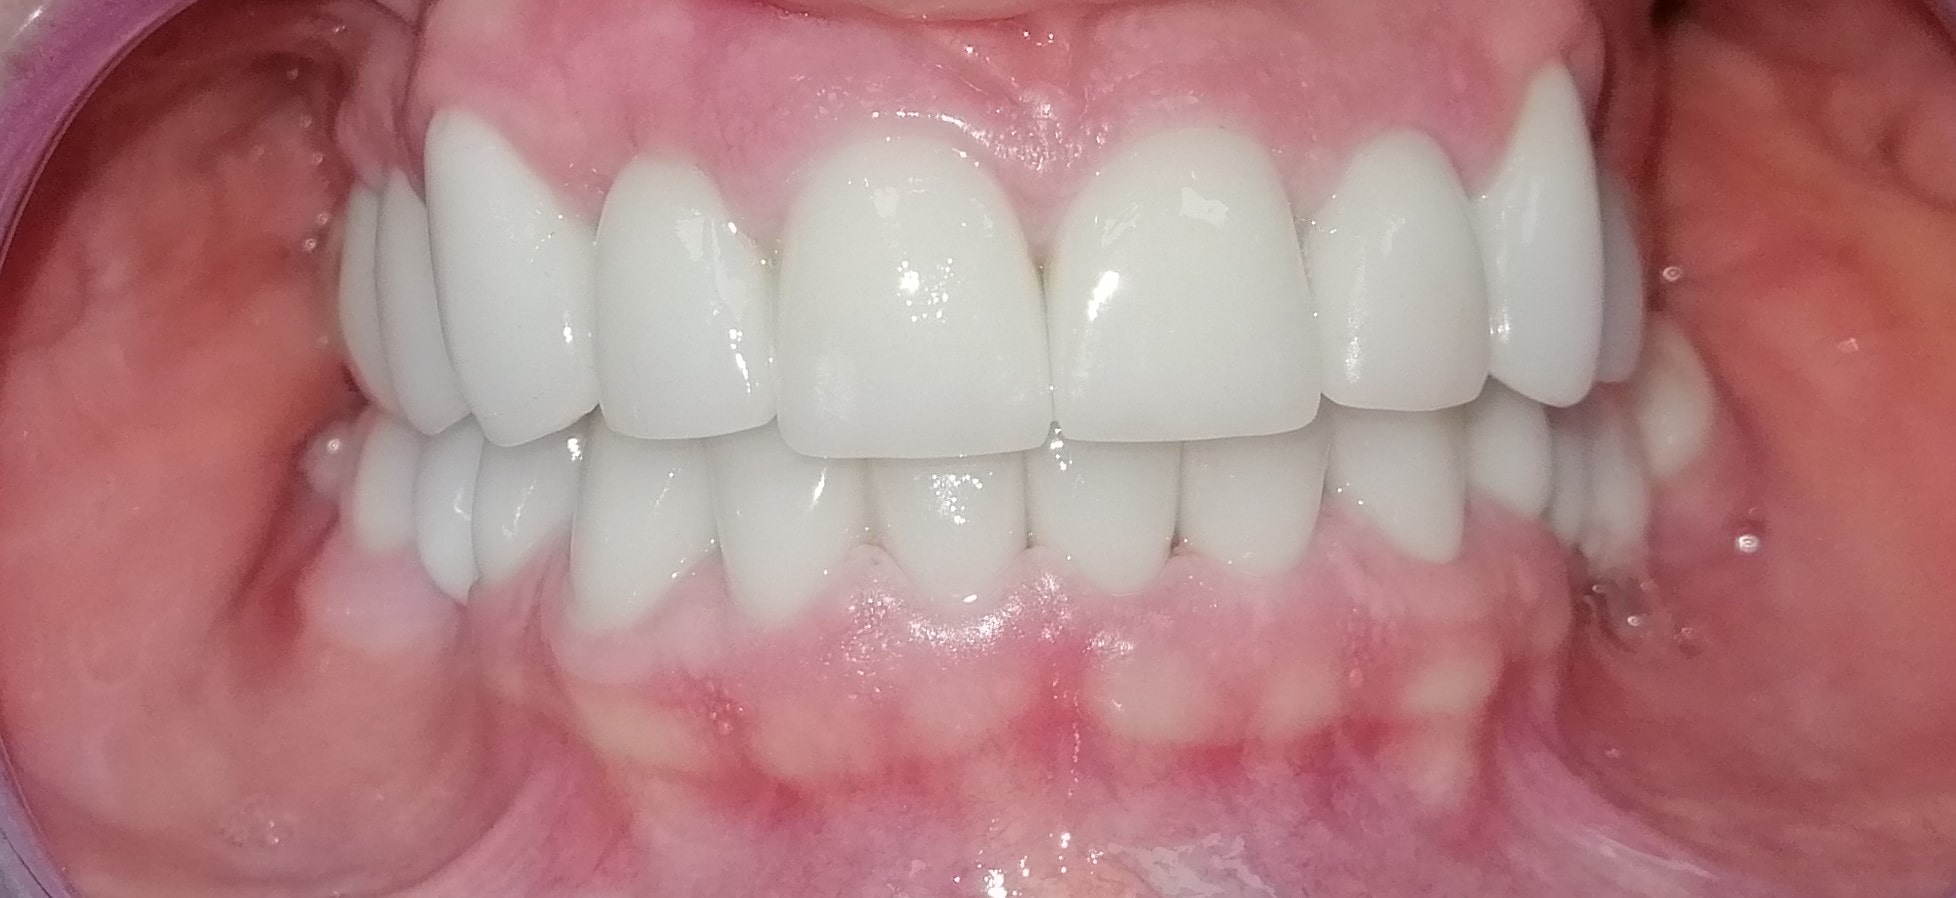

Pacijent 1

Pacijent iz Nemačke, kod koga smo estetsko i funkcionalno zbrinjavanje rešili cirkonijum keramičkim krunicama sa ugradnjom kratkih implantata u donjoj vilici zbog smanjene visine kosti, a u gornjoj vilici na levoj strani odmah nakon vađenja zuba je ugrađen standardni implantata na mesto izvađenog zuba i ugrađen je tuberopterigoidni implantat da se ne bi radila komplikovana sinus lift procedura koja bi produžila vreme završetka rada na godinu i više dana. Rad uspešno završen i pacijent nema nikakvih problema već pet godina.